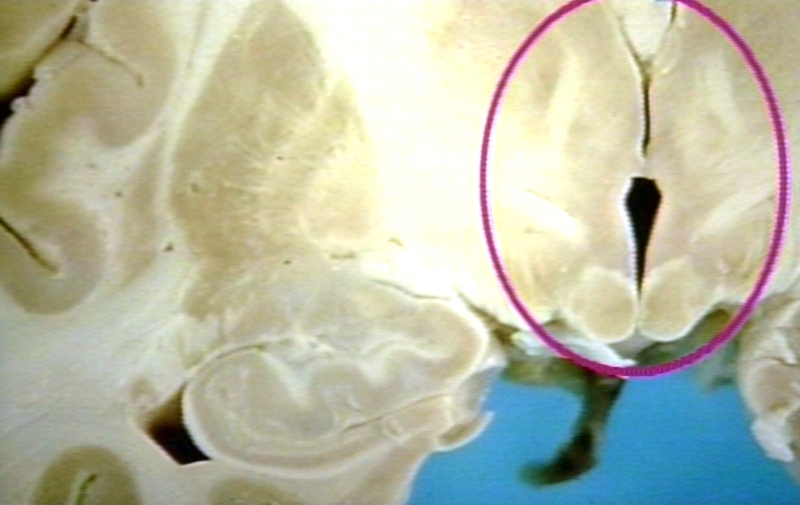

GROSS: NERVOUS: THALAMUS: DIENCEPHALON, HYPOTHALAMUS AND THALAMUS

gross, nervous, thalamus